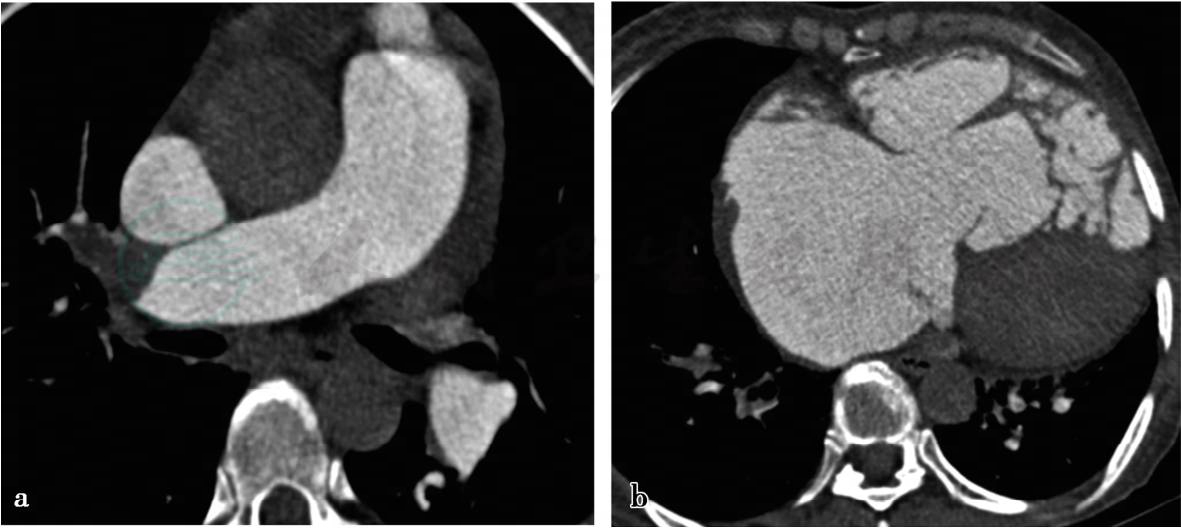

(2)病例5:

心脏与肺CT增强。

图2 图2a,双肺动脉多发低密度充盈缺损。图2b,肺动脉增粗,主肺动脉径约3.9cm,右心房、右心室明显增大

(2)病例5,慢性肺栓塞。